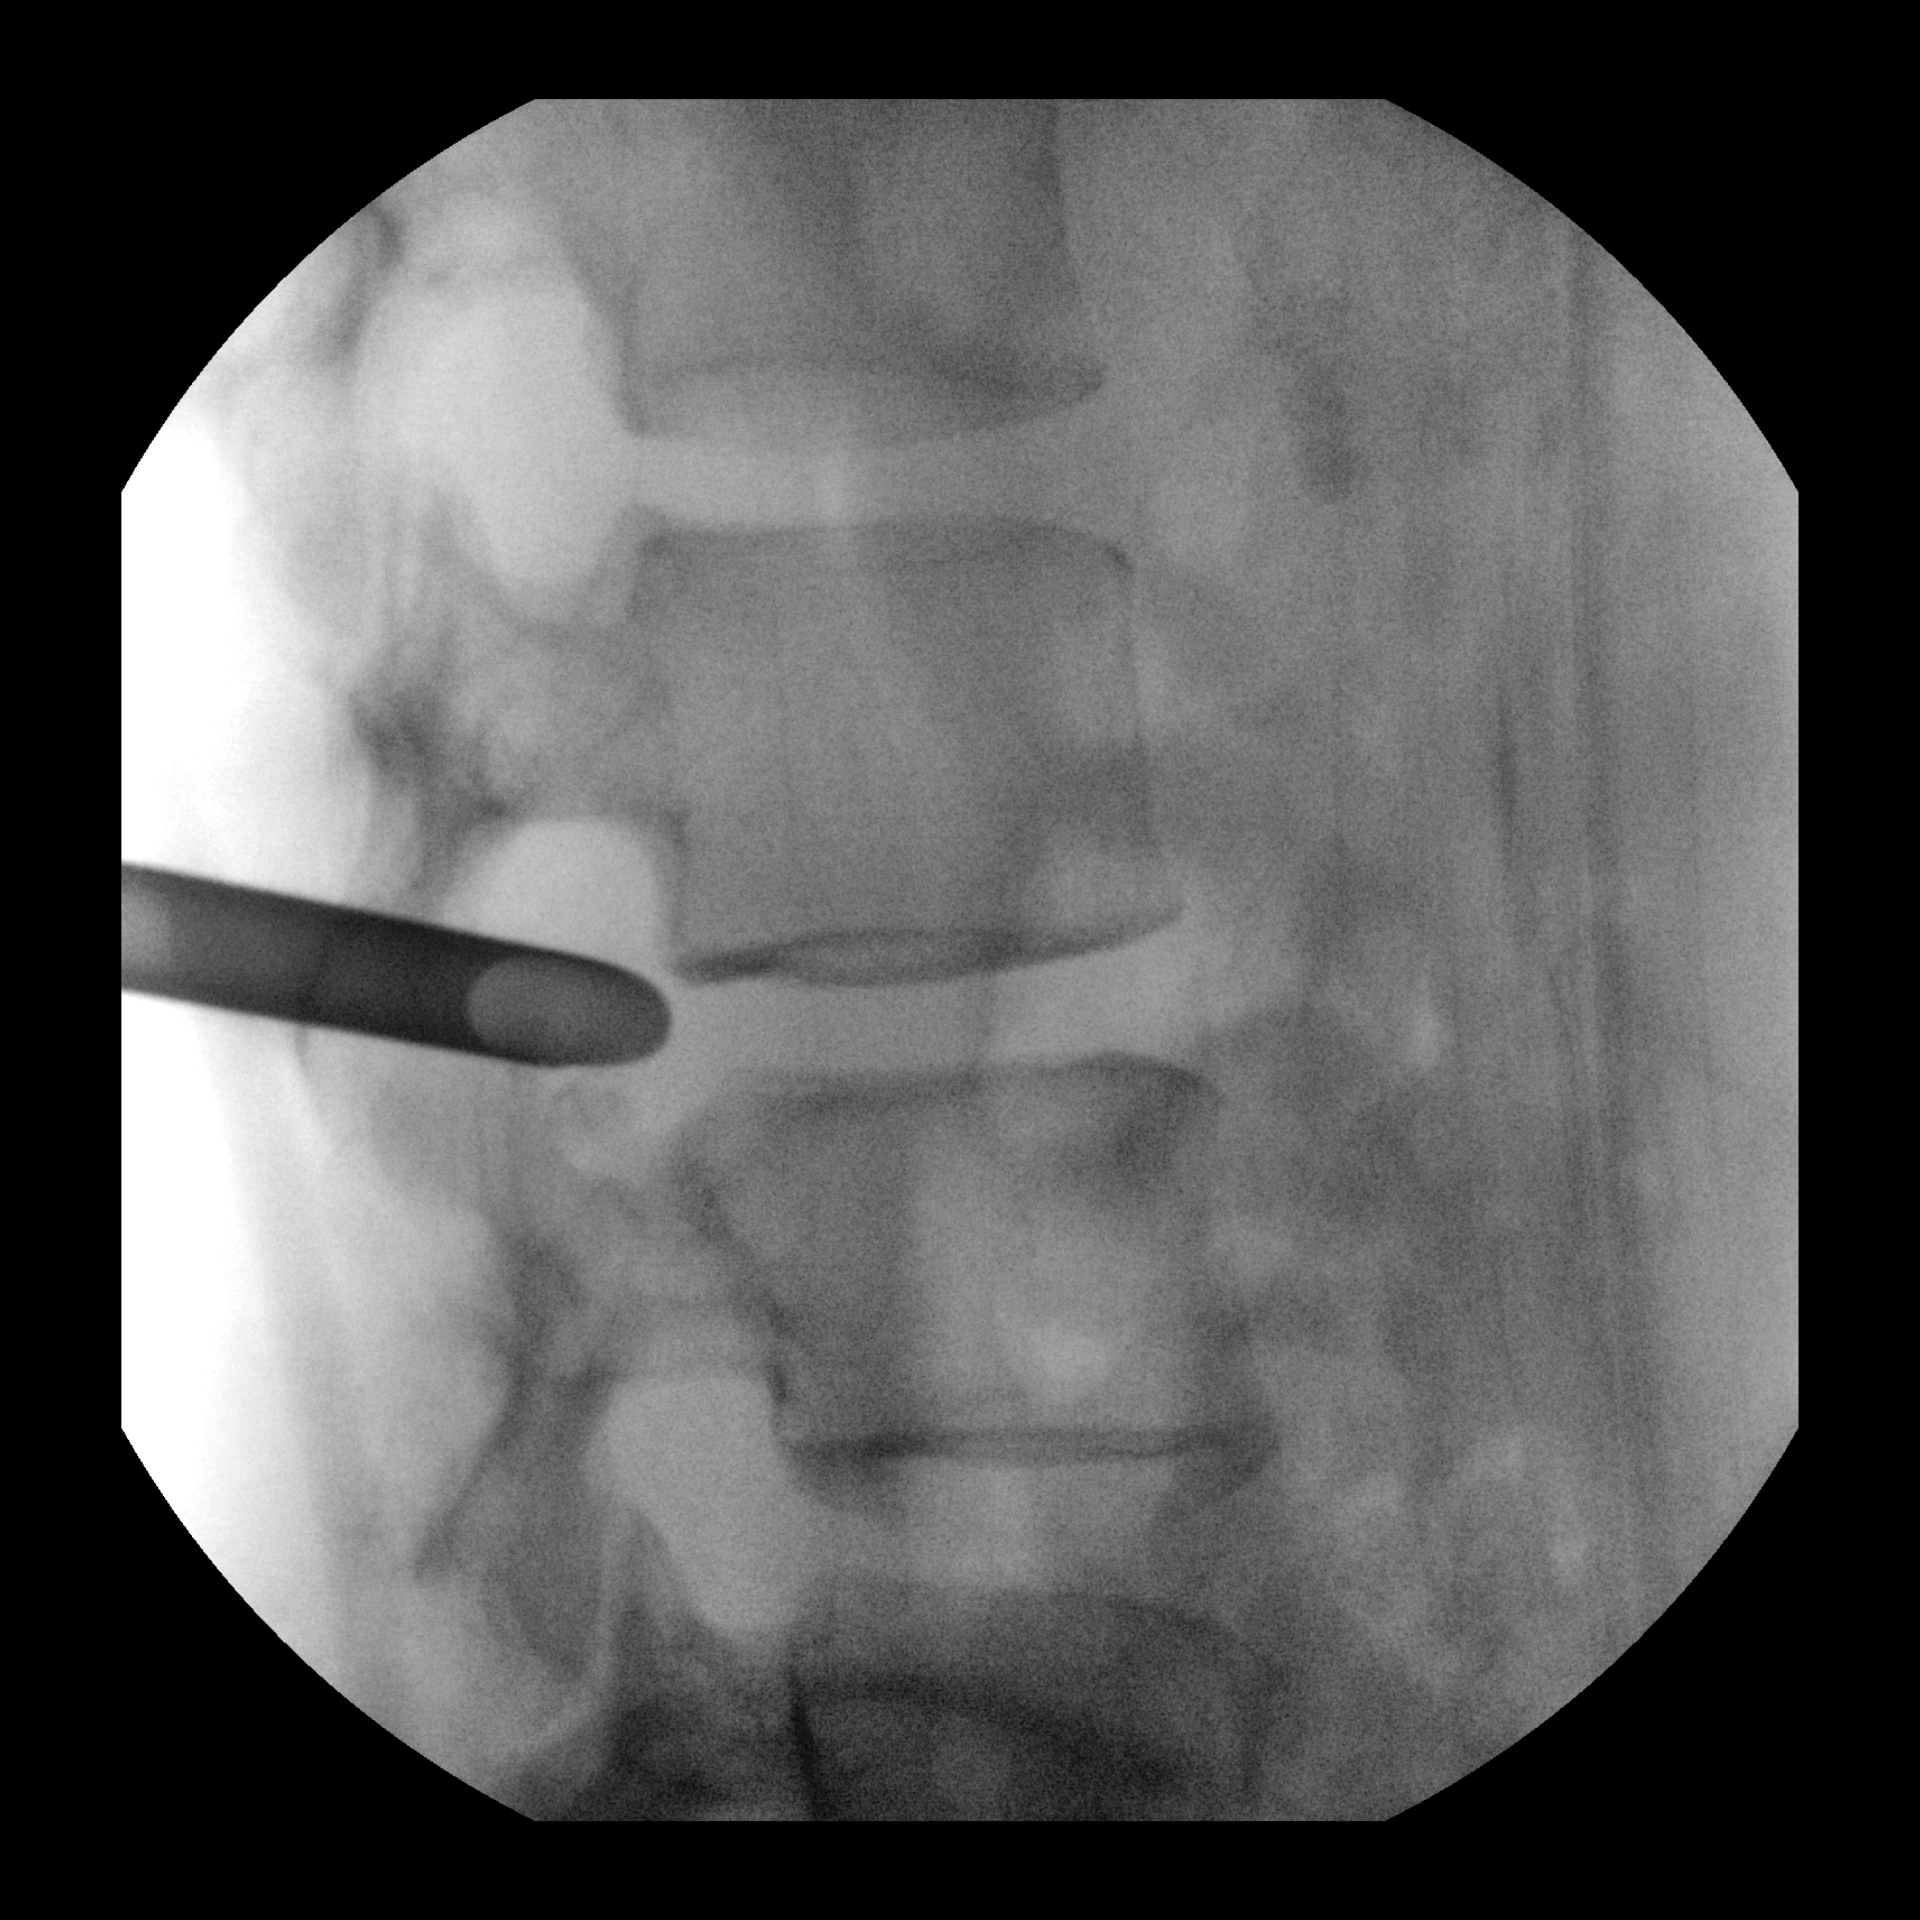

Advanced Features such as Live zoom for dose level optimization

View 4x image size with Live Zoom without increasing the dose (vs Magnification modes) and visualize guidewires

as small as 0.014” in peripheral vascular procedures.

as small as 0.014” in peripheral vascular procedures.